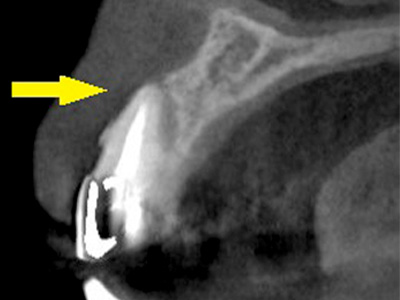

CTで見ると、骨が薄いのが良く分かります。

黄色の矢印の部分、白く写るのが骨で矢印のある黒い部分が上顎洞という空洞です。 -